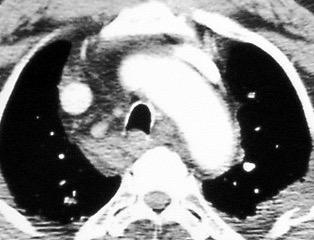

Linfoma de Hodgkin escleroso-nodular

Mediastinitis fibrosa. Fibrosis retroperitoneal.

10-20% de los casos de FM difusa

Reacción a Enf. Autoinmunes. (LED, AR)

Hematopoyesis extramedular

Metersigida / Radioterapia. Enf. inmunoglobulina IgG4. (Riedel, Colangitis, etc.)